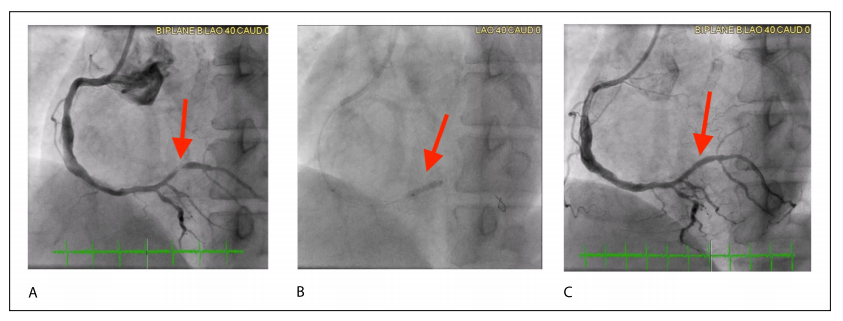

表1突出了展示DCBs在ISR中性能的主要随机对照试验(RCTs)。AGENT IDE(评估Agent紫杉醇涂层PTCA球囊导管治疗支架内再狭窄受试者的临床试验)试验在混合ISR中突出了DCB治疗策略优于POBA。该研究的1年结果显示,与POBA组相比,靶病变失败(TLF)、靶病变血运重建(TLR)和靶血管相关心肌梗死显著减少,使得美国食品药品监督管理局批准AGENTTM DCB(波士顿科学公司)用于ISR。最近,AGENT IDE试验的2年数据也与先前结果一致,显示DCB组事件和重复干预更少。其他几项比较DCB与POBA的研究显示DCB的血管造影和临床结局更优。图3说明了AGENT DCB用于ISR的成功应用。

图3 冠状动脉造影图像展示使用药物涂层球囊(DCB)治疗支架内再狭窄(ISR)。(A) 术前图像显示靶血管存在90%的ISR。(B) 术中释放2.5 × 15 mm的AGENT药物涂层球囊,以6个大气压扩张60秒。(C) 术后图像显示DCB干预后ISR完全缓解,狭窄率为0%。